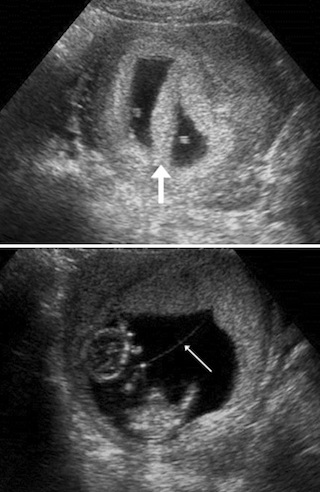

# **1. MISSED ABORTION – ULTRASOUND FINDINGS**

### **Definition:**

Embryo/fetus has died but is retaine...